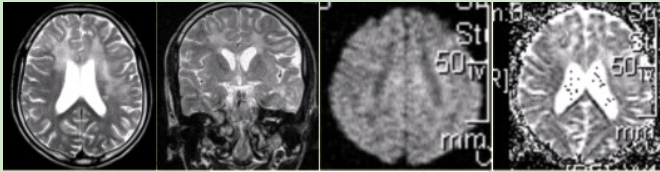

男性,16岁,头痛2年,加重1个月。MR检查如下图。 可能的诊断是

可能的诊断是

A.大脑胶质瘤病

B.脑转移瘤

C.病毒性脑炎

D.急性脑梗死

E.多发性硬化

[单选题]男性,16岁,头痛2年,加重1个月。MR检查如下图。有关该病的描述正确的是A.TWI上为高信号,占位效应明显B.弥漫性肿瘤浸润,相应脑结构正常C.与白

[单选题]男性,16岁,头痛2年,加重1个月。MR检查如下图。该病的影像学表现,不正确的是A.TWI显示多个脑叶的弥漫性高信号B.DWI上呈等信号,ADC上呈高

[单选题]男性,16岁,头痛2年,加重1个月。MR检查如下图。可能的诊断是A.大脑胶质瘤病B.脑转移瘤C.病毒性脑炎D.急性脑梗死E.多发性硬化